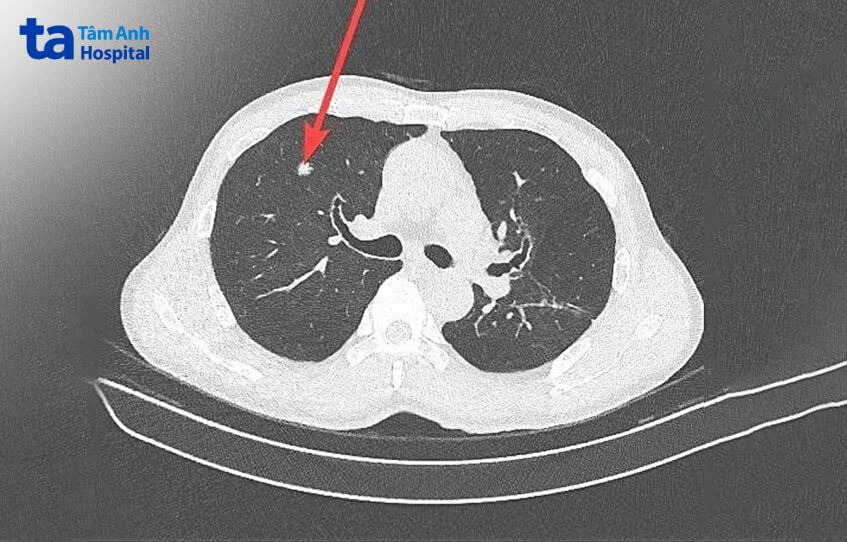

Hiện nay, phương pháp tầm soát ung thư phổi thường được chỉ định gồm chụp CT phổi liều thấp hoặc chụp X-quang phổi, nội soi phế quản ống mềm… cho kết quả nhanh chóng, độ chính xác cao, không đau nhức, tạo sự thoải mái cho người bệnh. Nhờ trang bị hệ thống chụp cắt lớp vi tính 768 lát cắt ứng dụng trí tuệ nhân tạo (AI) cho hình ảnh 3D có thể nhìn thấy phổi từ nhiều hướng, tại bệnh viện Tâm Anh, những u phổi kích thước nhỏ 2-3mm có thể được phát hiện qua chụp CT phổi liều thấp. Từ đó, bác sĩ có thể đưa ra kế hoạch điều trị phù hợp ở giai đoạn sớm, tăng tỷ lệ sống còn sau 5 năm cho người bệnh.